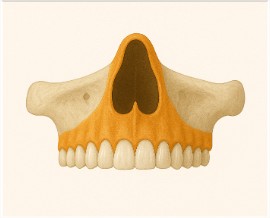

🎯 1. Tomografia da Maxila Completa

Usada para:

-

Implantes superiores

-

Avaliação dos seios

-

Cistos e lesões superiores